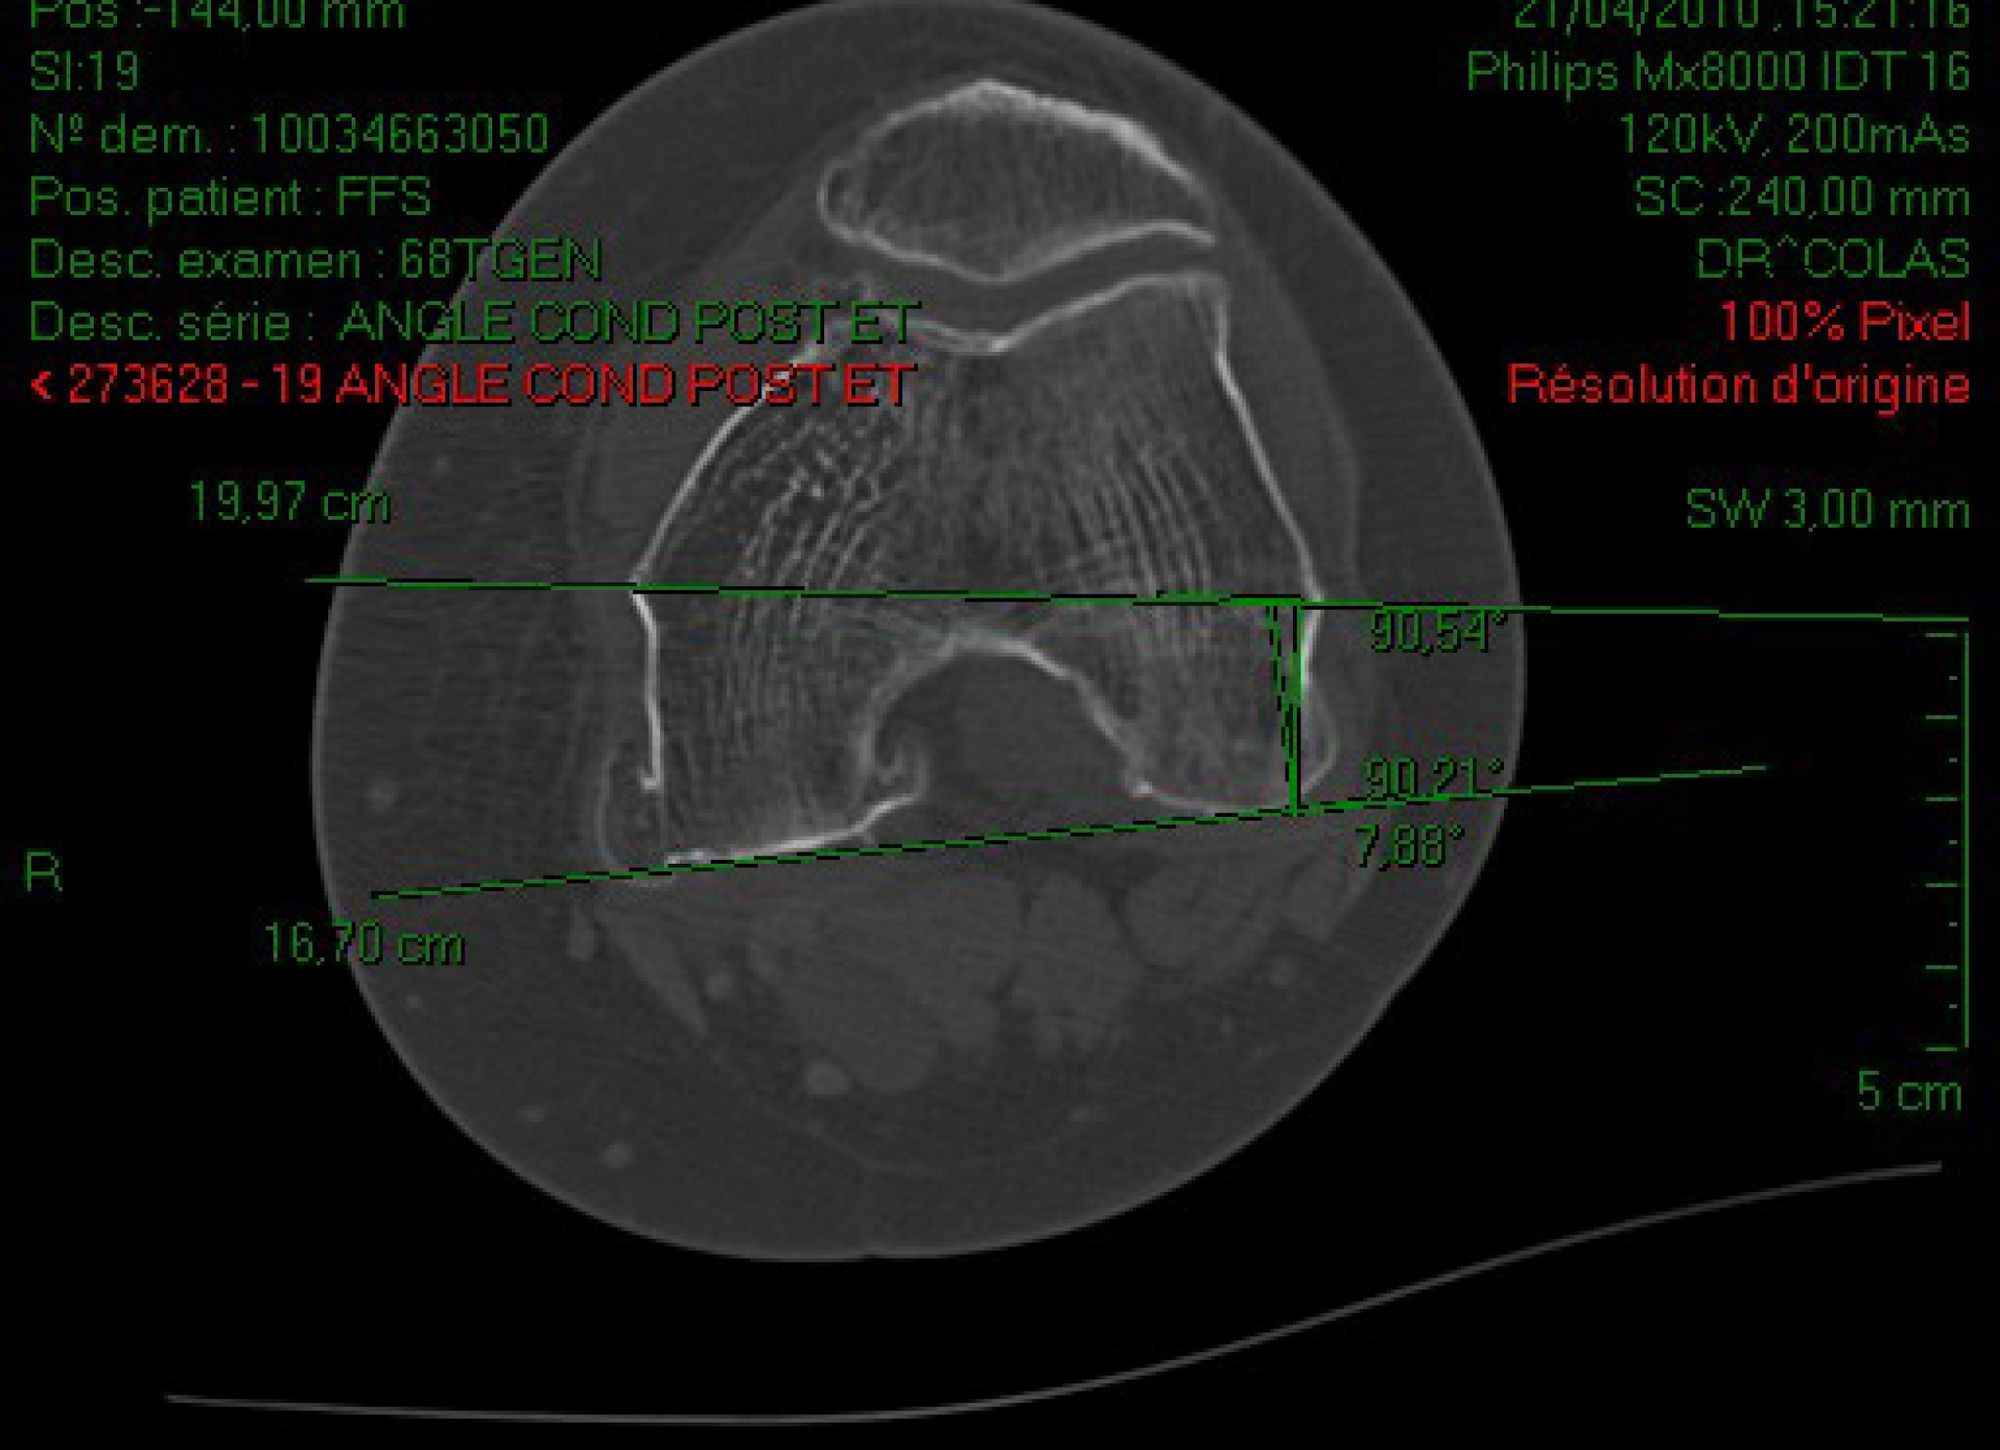

The flexion gap was assessed, after adjusting for rotation, by measuring the medial and lateral tibiofemoral space during forced varus and valgus stress with the knee at 90° and the patella reduced (Figure 8). In one centre, the CT measurement of the posterior condylar angle was performed preoperatively. At the time of operation, the surgeon was blinded to these result (Figure 9). All of the digital data were stored in the navigation system and then combined with the clinical data in a spreadsheet (Microsoft Excel©). The statistics were handled by SPSS© software (IBM SPSS Analysis, IBM, Armonk, New York, USA).

Data gained with the navigation system compared to the CT scan are summarized in Table 1. The difference between the two average values is 1.5°. Note the absence of negative angles (= internal rotation), with both the navigation system and computed tomography. Figure 11 demonstrates the correlation between the values from the two methods. The difference observed between the two centres (averages of 4.3° and 5°) is not significant (Figure 12). Furthermore, a non-parametric Wilcoxon test, based on the hypothesis that the median of the differences between the angle produced by the CT scanner and the angle produced by the navigation system is equal to 0, is significant (p<0,01). This confirms good concordance between the angles produced by the two methods.

The results presented in Table 1 enable us to confirm, like many other authors, the great individual variability of the posterior condylar angle ranging from 0 to 11° (8, 20-25). This variability dooms any method that establishes external rotation a priori at a fixed, predetermined value (often 3° for supporters of this technique). In this study, the average posterior condylar angle produced by the navigation system is very close to that found by the computed tomographic studies (5° versus 6.5°). For a given angle value, the measurements obtained by the two methods are correlated with one another and concordant (Figure 11). Furthermore, the two different centres using the same technique obtained similar results (Figure 12). These results as a whole demonstrate that trochlear navigation is a reliable and reproducible method for adjusting the femoral casing in rotation.